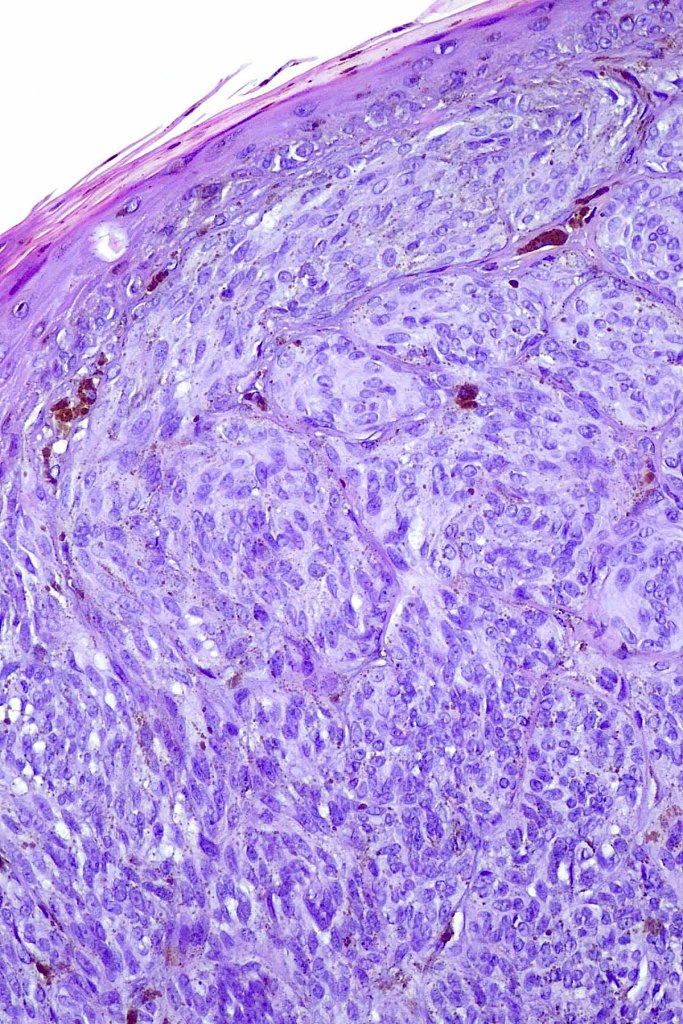

•Sharply circumscribed (begins and ends with a nest), symmetrical dome-shaped lesion. Symmetry is both horizontal and vertical (see image below)

•Wedge-shaped with the base uppermost or sometimes plaque-shaped silhouette

•Hyperkeratosis & acanthosis, sometimes very marked

•Pseudoepitheliomatous hyperplasia

•Superficial vascular ectasia very frequently present

•Lymphocytic infiltration at the base of the lesion